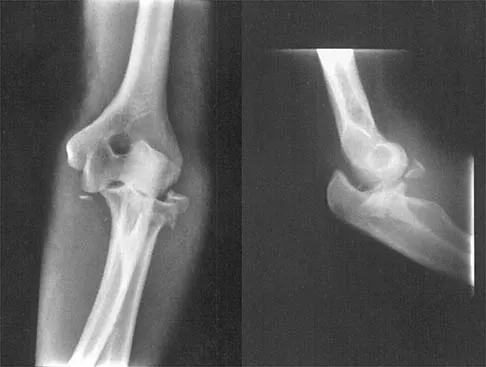

Figure 40 shows the radiograph of a 16-year-old wrestler who injured his elbow when he was thrown to the mat by his opponent. Closed reduction is readily accomplished, and the elbow seems stable. Management should now consist of application of a splint for

Flexion contractures are the most common complication of elbow dislocations. About 15% of patients lose more than 30 degrees of flexion. The risk of contracture is proportional to the duration of immobilization. Elbows should be moved within the first few days after reduction. The splinting is for comfort and protection only while the pain subsides. Mehlhoff TL, Noble PC, Bennett JB, Tullos HS: Simple dislocation of the elbow in the adult: Results after closed treatment. J Bone Joint Surg Am 1988;70:244-249. Linscheid RL, O'Driscoll SW: Elbow dislocations, in Morrey BF (ed): The Elbow and Its Disorders, ed 2. Philadelphia, PA, WB Saunders, 1993, pp 441-452. O'Driscoll SW, Jupiter JB, King GJ, Hotchkiss RN, Morrey BF: The unstable elbow. Instr Course Lect 2001;50:89-102.